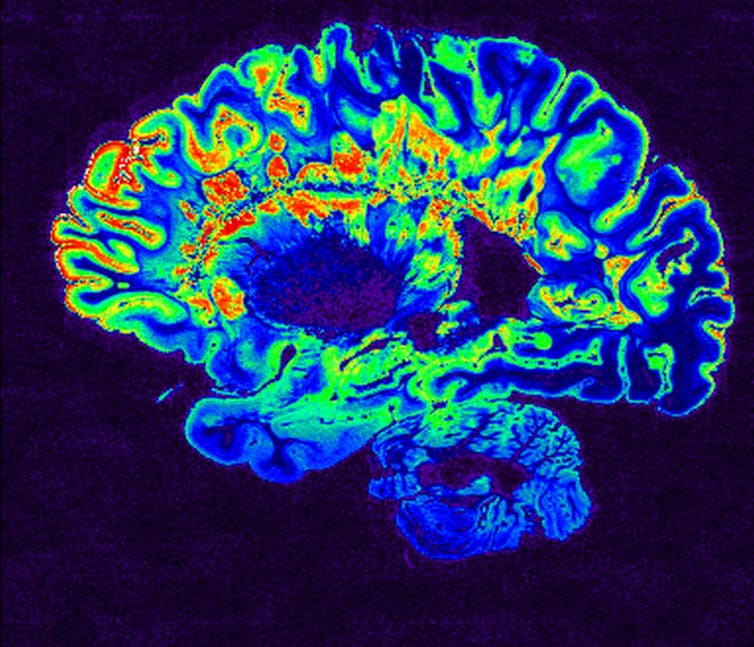

One way of finding out more is to take a look inside patients’ heads using brain-imaging techniques, such as MRI. So far, brain imaging has revealed a pattern of previously unseen findings, but its still very early days for using it in this pandemic.

In one study, patterns found included signs of inflammation and a shower of small spots of bleeding, often in the deepest parts of the brain. Some of these findings are similar to those seen in divers or in altitude sickness. They might represent the profound lack of oxygen being delivered to the brain in some patients with COVID-19 – but we are only starting to understand the full scope of the brain’s involvement in the disease. Brain-imaging and postmortem studies for those killed by COVID-19 have been limited to date.